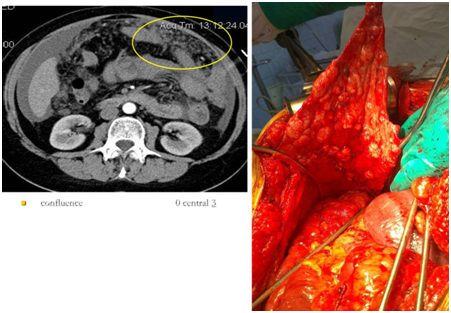

Figure 4 CT image of implants of right lateral canal and right iliac region.

Figure 7 Implants of hepatorenal recess of peritoneum (Morrison pouch) on CT scan and intraoperative image.